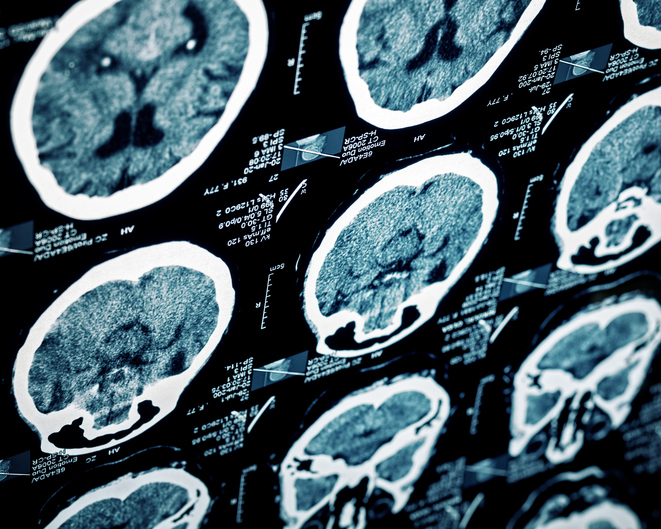

Chances are, you might not have known that March is Brain Injury Awareness month. In fact, unless yourself or a loved one has ever suffered from a Traumatic Brain Injury (TBI), you might not also know that TBI’s account for a great portion of deaths and disabilities in the U.S. and cost a stunning $76 billion every year (Centers for Disease Control).

Known mostly by its sufferers as the “invisible disability,” TBI’s often go undetected. Because most signs of a TBI aren’t visible, it is no wonder that those dealing with the pain of having one might feel alone in their struggle. However, nothing could be further from the truth.

Traumatic Brain Injuries affect 2.5 million children and adults every year.